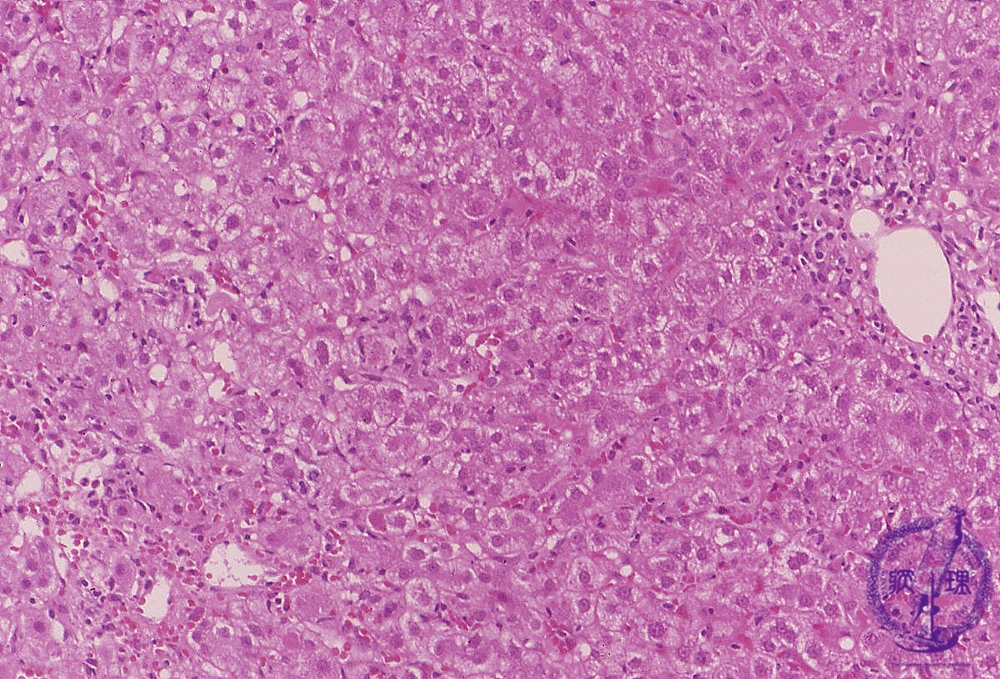

- 10.Liver

- ★(1)Acute viral hepatitis

Microscopic finding (HE stain): There is diffuse involvement of lobules throuought the liver. Hepatocellular swelling, focal necrosis and inflammation are especially noticeable in the centrilobular area (image, lower left). Additionally, there is a periportal inflammation (image, upper right).

Click the image to see the enlarged image.